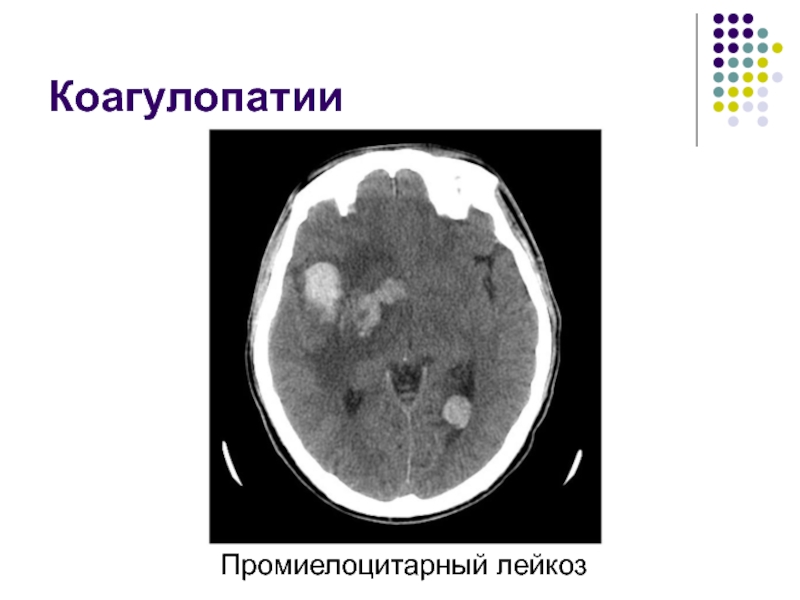

Слайд 34Коагулопатии

Нарушение свертываемости крови

Большая группа заболеваний, включающая в себя прием препаратов,

изменяющих свойства крови, тромбоцитопении, опухоли, тромбоцитопеническую пурпуру и другие

Слайд 35Коагулопатии

Промиелоцитарный лейкоз

Коагулопатии Промиелоцитарный лейкоз